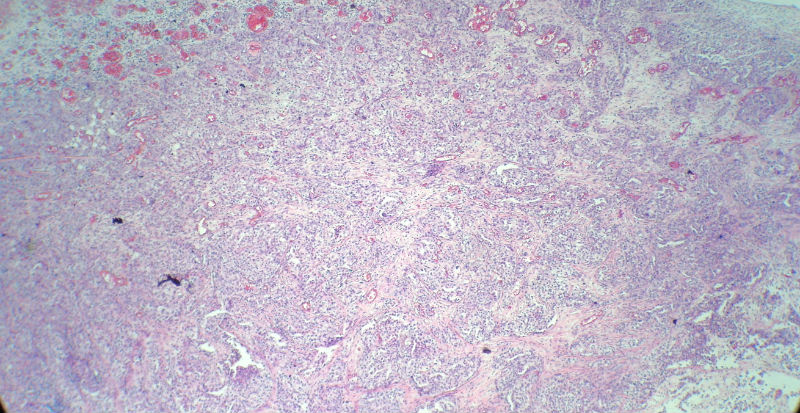

男,82岁,小肠穿孔紧急手术。

大体,小肠一段,长约60厘米,与粘膜面可见三个溃疡型肿物,肠系膜淋巴结肿大。

肿瘤呈巢片状分布,细胞大小相对一致,胞浆丰富,胞核呈细颗粒状,可见小核仁,血管较丰富,考虑神经内分泌肿瘤,加做免疫组化(Ki67、Syn、NSE、CgA、CD56)分级。